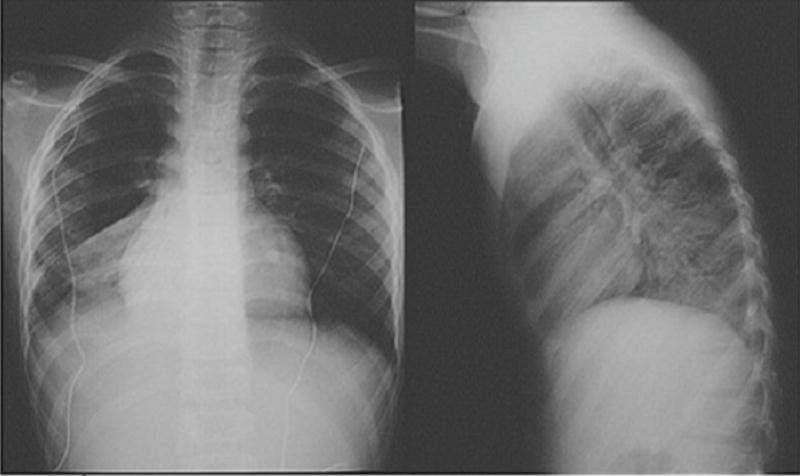

Cảnh báo: tổng hợp ảnh bệnh lao phổi chân thực này không dành cho người yếu tim. Đây là loạt hình ảnh y khoa được các chuyên gia sưu tầm và xác thực, ghi lại quá trình tiến triển của bệnh từ giai đoạn đầu đến giai đoạn nguy kịch. Từng mảng mô phổi bị ăn mòn, xơ hóa, hoại tử được phơi bày rõ nét dưới ánh sáng X-quang lạnh lùng. Những hình ảnh này không chỉ mang tính chất minh họa y học, mà còn là hồi chuông cảnh tỉnh cho bất kỳ ai còn lơ là với căn bệnh nguy hiểm này.